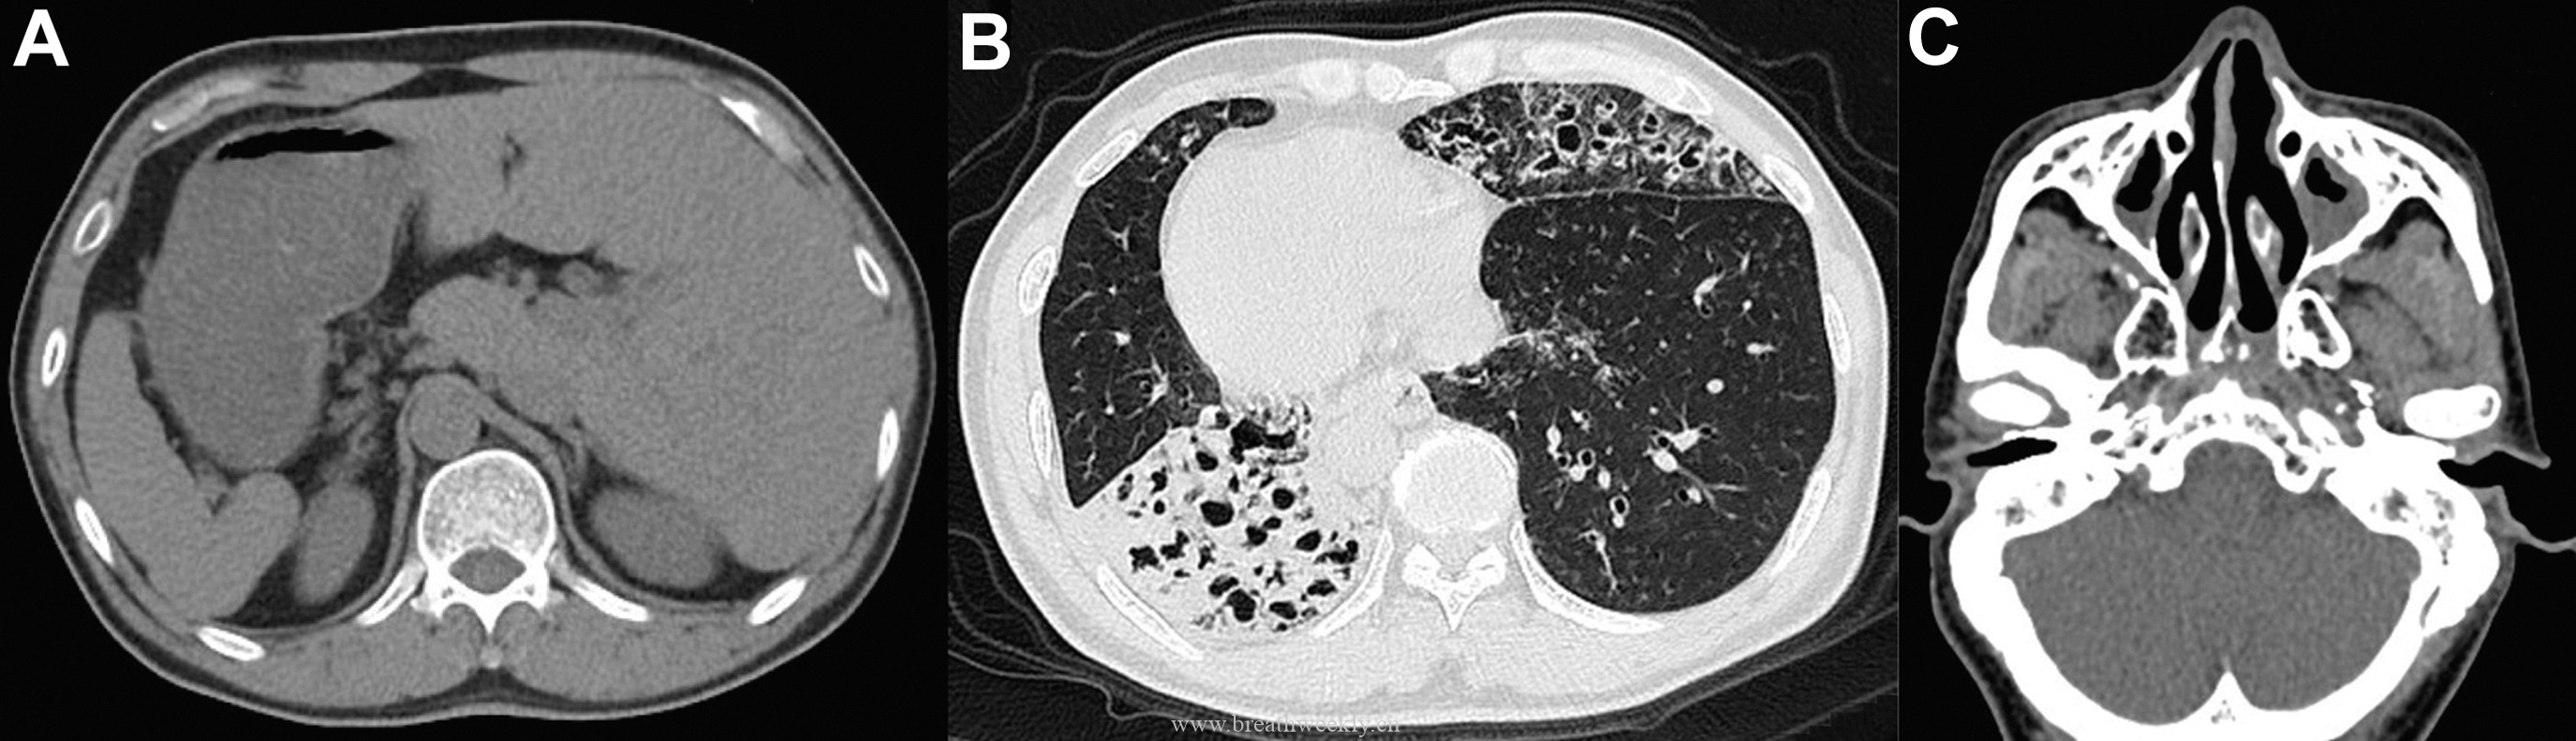

影像学检查

头颅CT除外颅内肿块及脑出血。脑及颈椎MRI(增强)除外CT隐性病灶,但发现右侧胸廓入口处囊性病灶。颈部超声及增强胸部CT:右侧上纵隔囊性占位,位于甲状腺右叶后下方,内见结节性实性成分及上极供血血管。胸部CT示前纵隔预期胸腺位置无异常软组织,提示胸腺脂肪萎缩。

⁹ᵐTc – 甲氧基异丁基异腈甲状旁腺显像:早期及延迟图像均可见甲状腺右叶下方异常摄取灶,摄取位于右上纵隔囊性病灶的实性成分内。

原发性甲状旁腺功能亢进症以高钙血症伴不适当正常或升高PTH为特征。典型表现为肾结石、骨病变(骨炎性纤维囊性变)。本例由单发甲状旁腺腺瘤引起,囊性变性罕见(仅1%-4%)。胚胎发育中,甲状旁腺来自第3、4咽囊,行程较长,故可异位于上纵隔。

临床过程:因纵隔病灶位置位于甲状腺右叶后下方,术前考虑异位胸腺瘤或异位甲状旁腺腺瘤。CT及超声示无claw sign,排除甲状腺来源。99mTc-Sestamibi显像定位病灶。MG予糖皮质激素及IV免疫球蛋白治疗效果良好;高钙血症予IV补液及cinacalcet治疗。最终行机器人辅助纵隔甲状旁腺腺瘤及胸腺切除术,病理确诊甲状旁腺腺瘤。术后患者恢复良好。